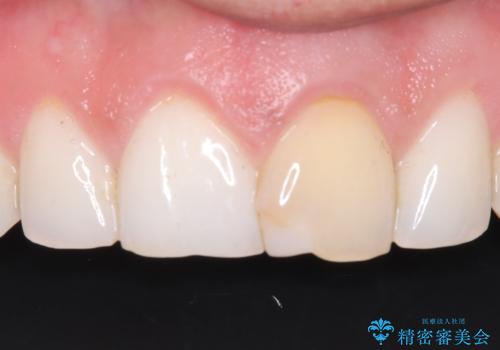

前歯の変色が気になる〈セラミッククラウン〉

過去に神経の治療をした歯に変色がみられました。ラバーダム防湿の重要性を説明し、予防的に再根管治療から行い、被せ物をすることとなりました。

なるべく隣の歯と調和するようにしました。大変ご満足いただけました。